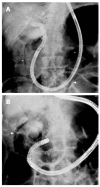

Endoscopic retrograde cholangiopancreatography (ERCP) in patients with surgically altered anatomy is challenging. Several operative interventions of both the gastrointestinal tract and the biliary and/or pancreatic system lead to altered anatomy, rendering ERCP more difficult or even impossible with a conventional side-viewing duodenoscope. Adapted endoscopes are available to reach the biliopancreatic system and to perform ERCP in patients with altered anatomy. However, both technical difficulties and complications determine the procedure's success. Different technical approaches have been described and are highly dependent on local expertise and endoscopic equipment. Standardized practical guidelines are currently unavailable. This review focuses on the challenges encountered during ERCP in patients with altered anatomy and how to deal with them. The first challenge is reaching the papilla or the bilioenteric/pancreatoenteric anastomosis in the patient with postoperative altered anatomy. The second challenge is the cannulation of the biliopancreatic system and performing all conventional ERCP interventions and the third challenge is the control of possible complications. The available literature data on this topic is reviewed and illustrated with clinical cases.